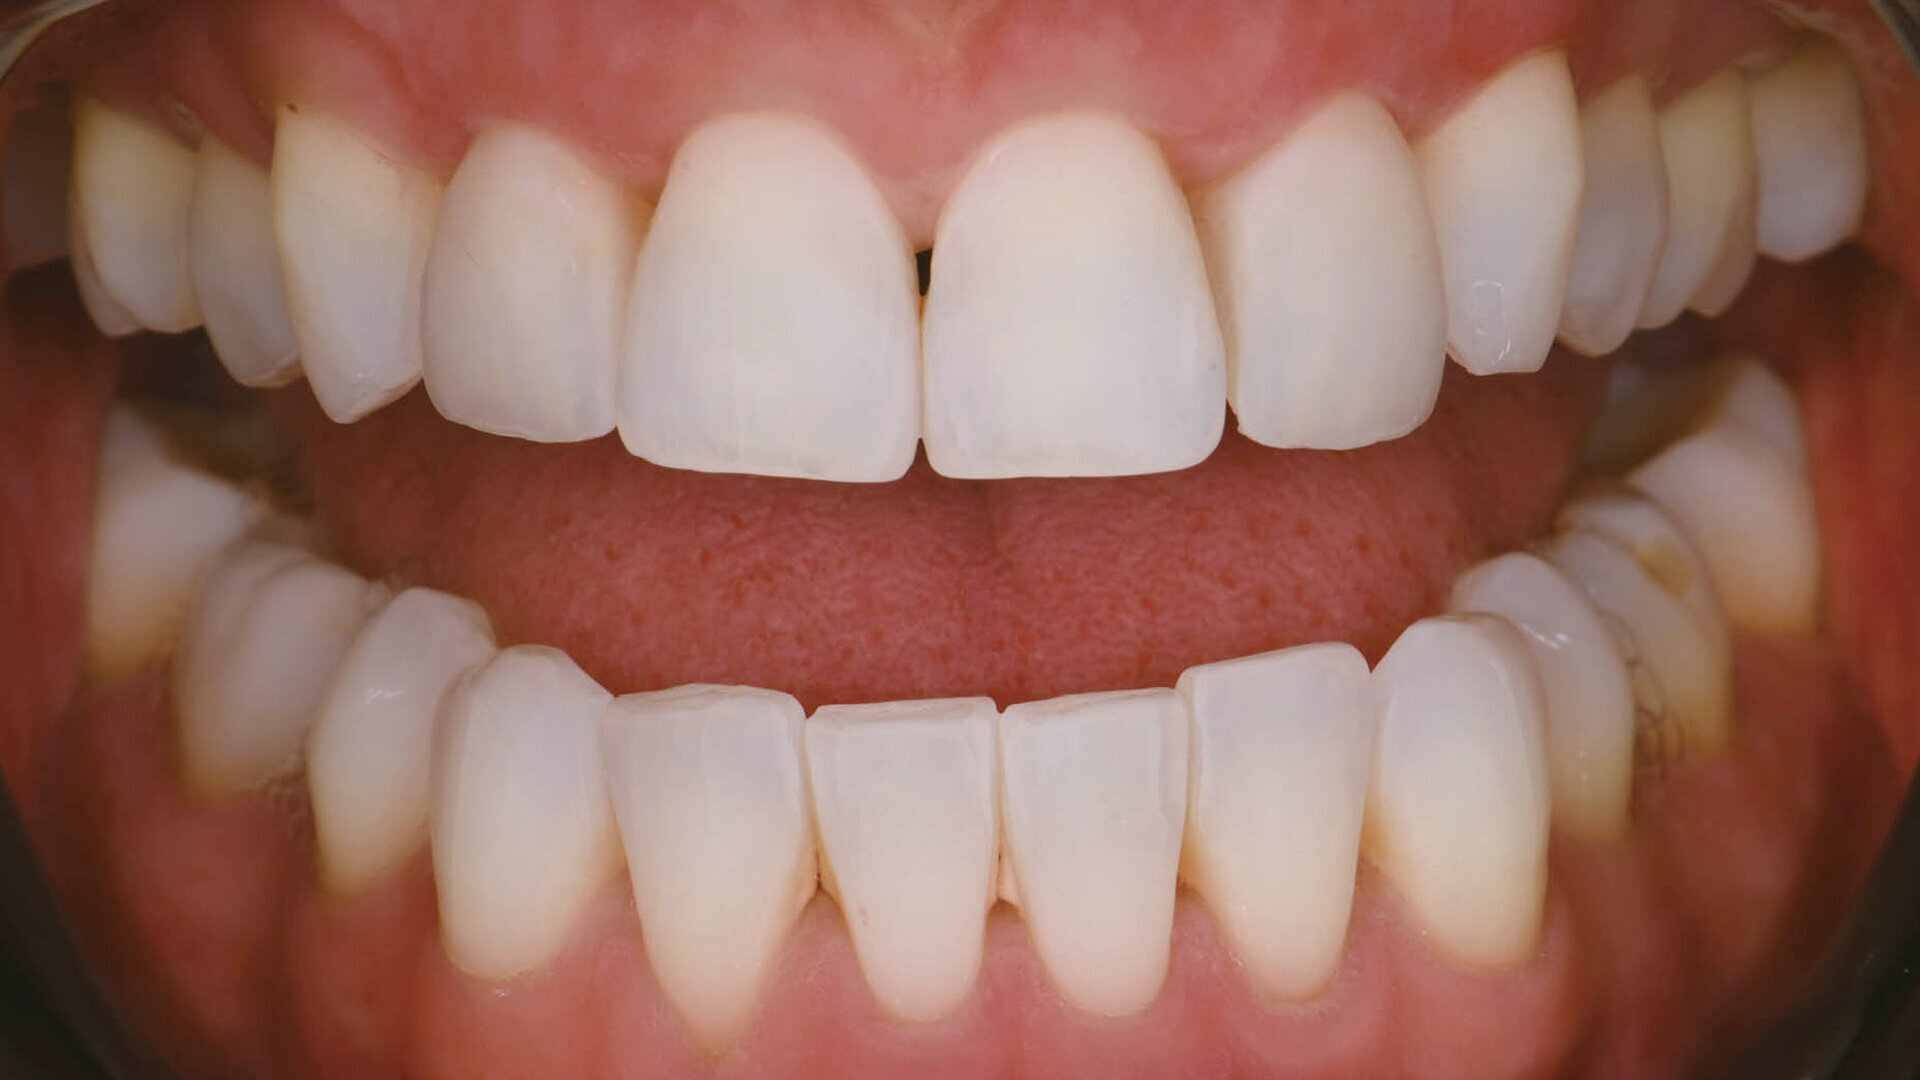

Final result of a veneer cementation procedure with polarised photography on reassessment. (All images: Clarence Tam)

The cement was rendered into a gel state, which facilitated clumping or en masse removal of cement, requiring minimal clean-up (Fig. 7). The margins were coated using a clear glycerine gel prior to final polymerisation to eliminate the oxygen inhibition layer (Fig. 8). The margins were finished and polished to a high shine and the occlusion of the restorations verified. The postoperative views showed excellent aesthetic marginal integration (Fig. 9). On polarised photograph reassessment, the restorations were found to be well integrated into the new smile aesthetically and functionally (Fig. 10), and aesthetic augmentation of tooth #23 to match the contralateral canine was awaited.

Fig. 10: Final result with polarised photography on reassessment.